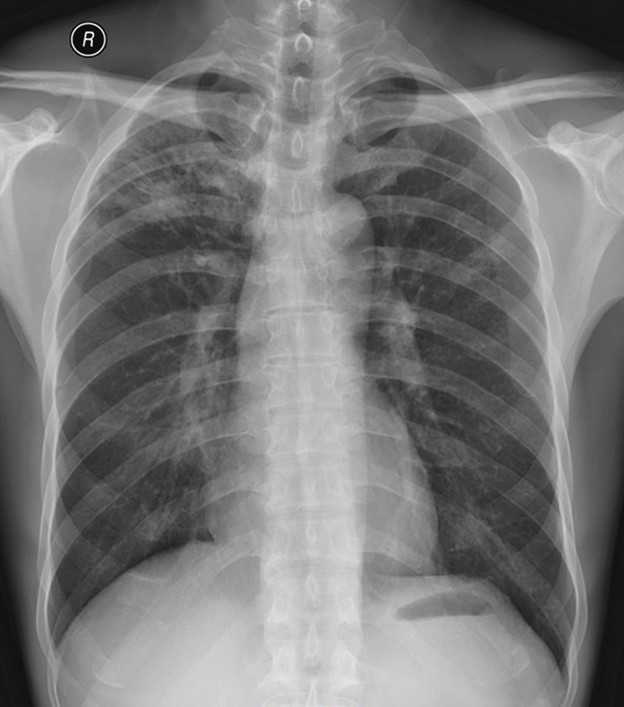

华夏览雄 达人已点赞患者,男46岁,病史已不详,乡镇卫生院胸片发现肺结核而转来本院检查。然后按结核治疗复查系列胸片,前后胸片相隔一个多月,其所见的是基本病变是否有变化呢?请分别描述一下应该是什么病变?

图(一)、第一次就诊拍的正位胸片: